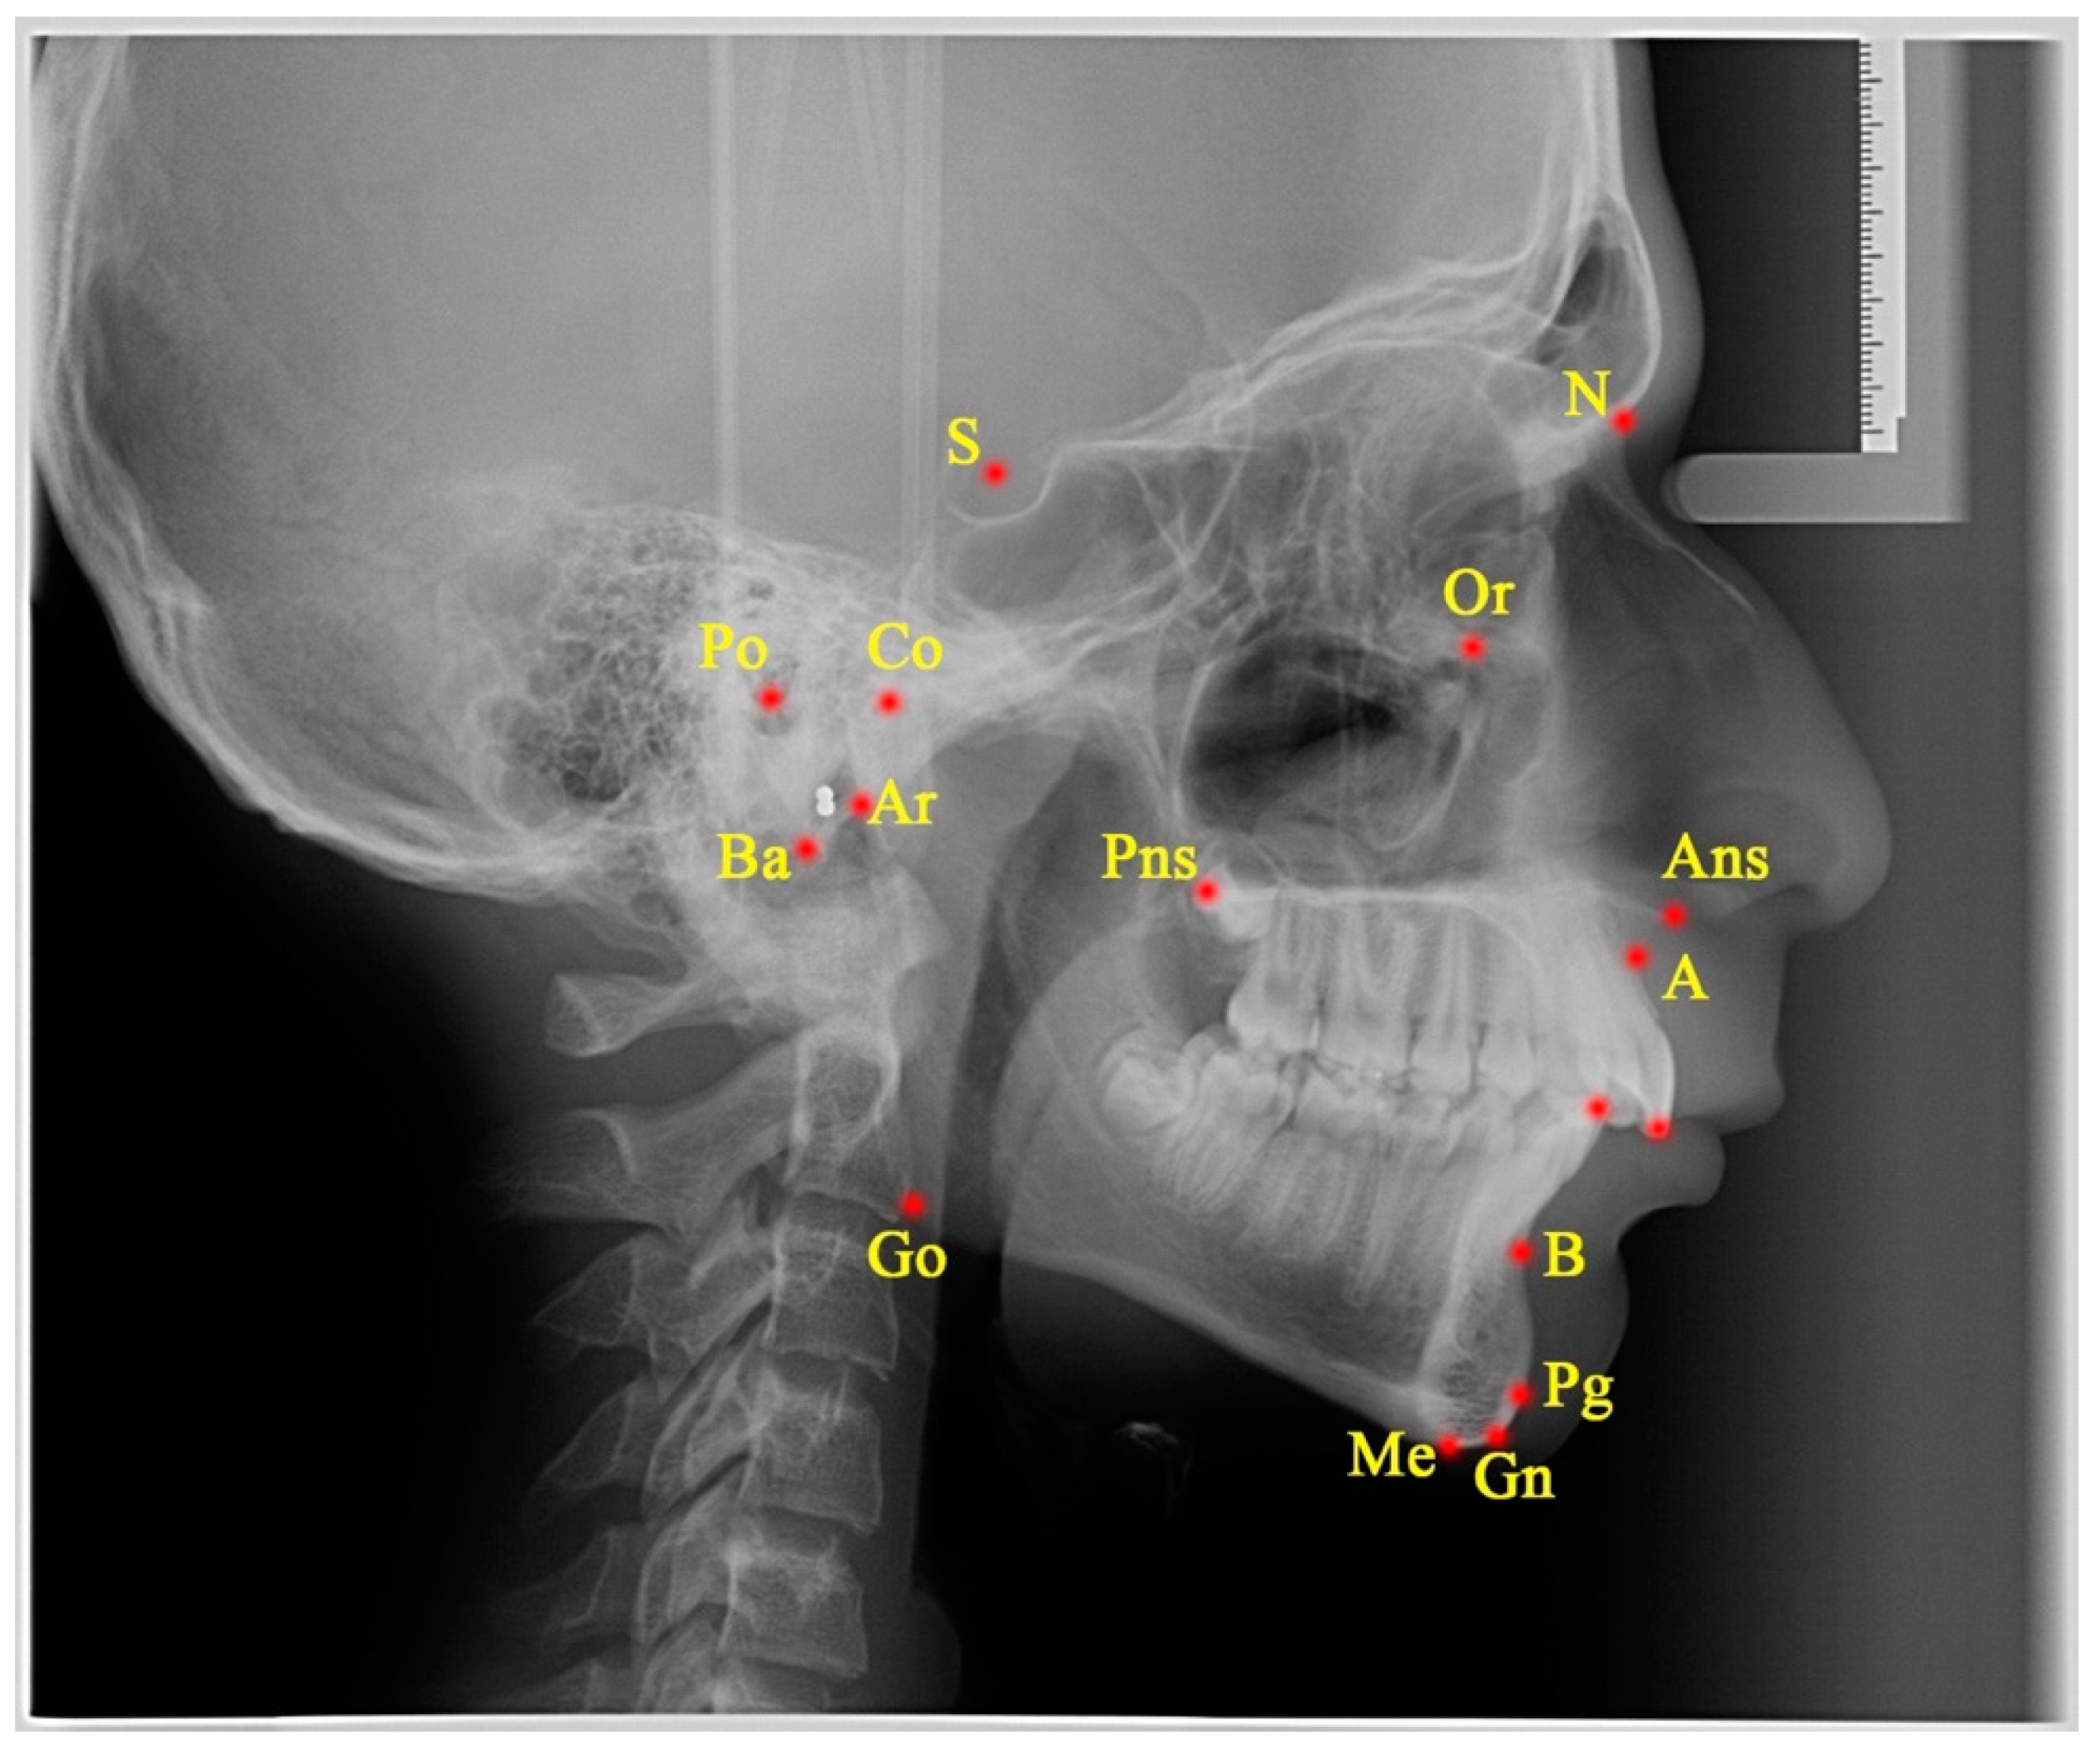

2.3. Measurements